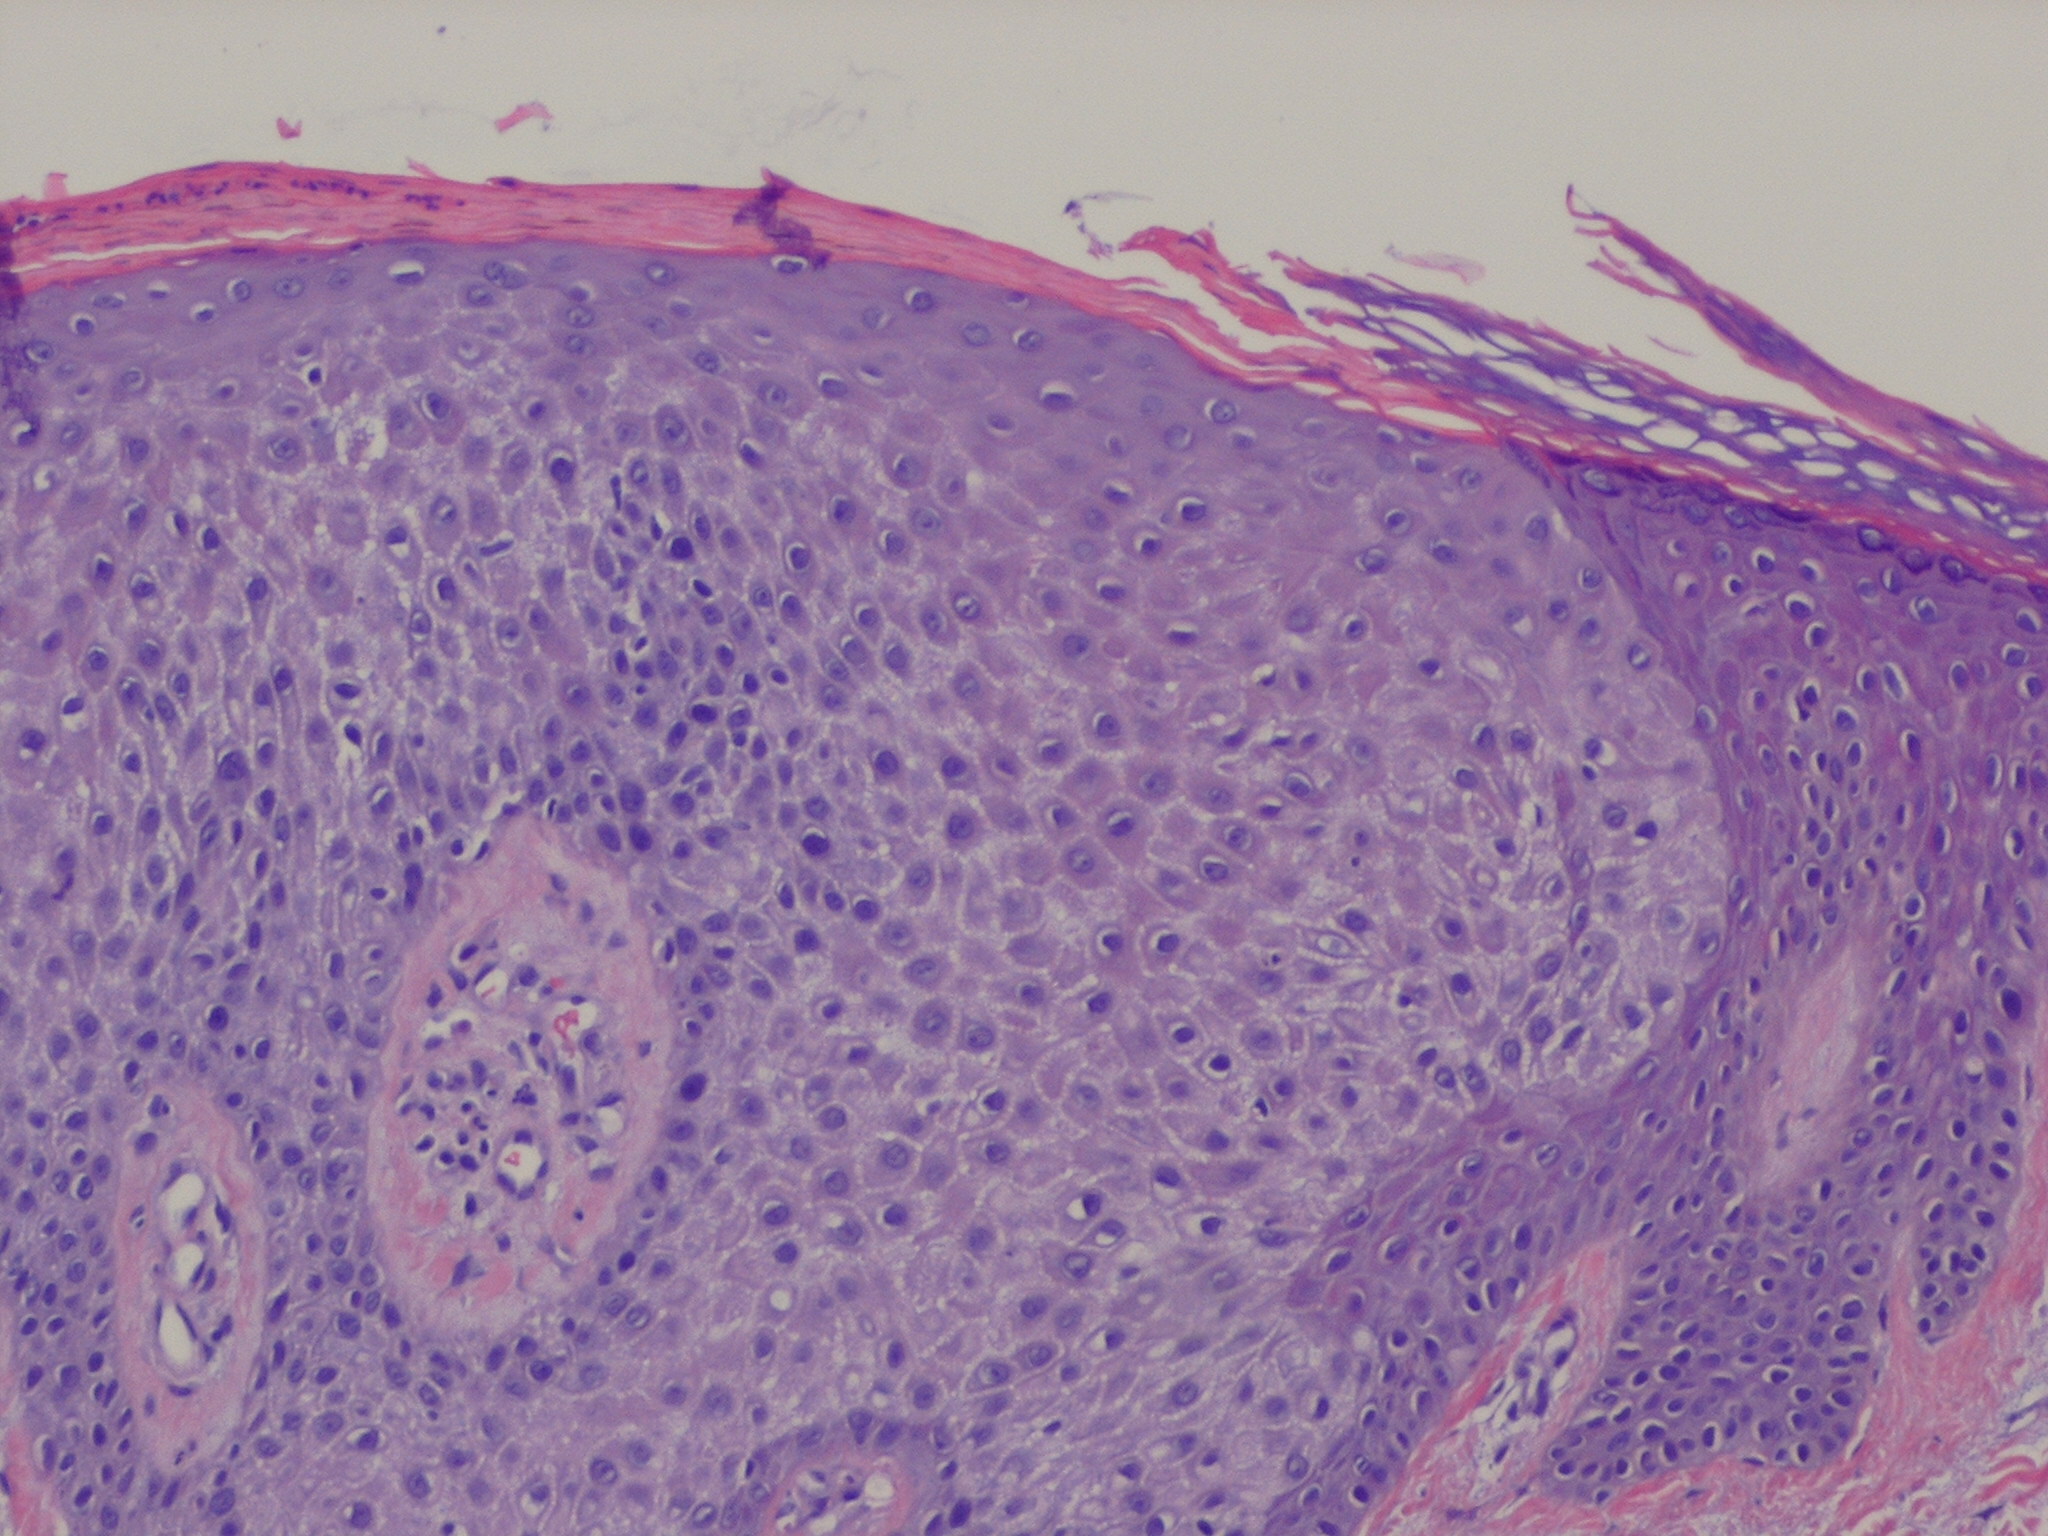

Within a sharply demarcated area of the epidermis

of cells of the basal cell layer, appear strikingly clear and slightly enlarged . The nuclei of the clear epidermal cells appear normal. When staining is carried out with the periodic acid-Schiff (PAS) reaction, the presence of large amounts of glycogen is revealed within the cells .

Slight spongiosis is present between the clear cells. The rete ridges are elongated and may show intertwining . The surface shows parakeratosis with few or no granular cells. The acrosyringia and acrotrichia within the tumor retain their normal stainability . There is an absence of melanin within the tumor cells, but dendritic melanocytes containing melanin are occasionally seen interspersed between the clear cells .

A conspicuous feature in most lesions is the presence throughout the epidermis of numerous neutrophils, many of which show fragmentation of their nuclei . The neutrophils often form microabscesses in the parakeratotic horny layer . Dilated capillaries are seen in the elongated papillae and often also in the dermis underlying the tumor In addition, a mild to moderately severe cellular infiltrate composed largely of lymphoid cells is present in the dermis. Some clear cell acanthomas appear papillomatous, so that they have the configuration of a seborrheic keratosis .